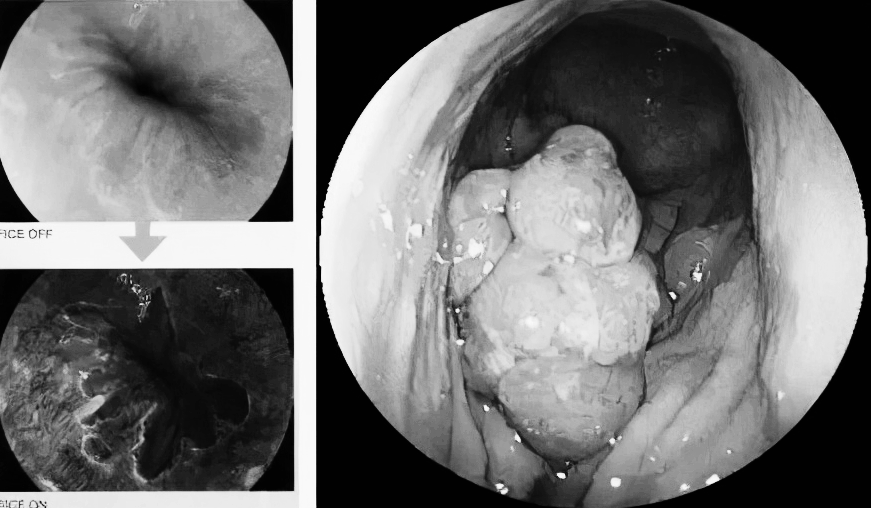

ʲôÊdz¦¾µ£¿³¦¾µ¼ì²é¾ÍÊÇͨ¹ý¸ØÃŲåÈëÒ»¸ùÈí¹Ü£¬Í¨¹ýÈí¹Üǰ¶ËµÄ¡°ÉãÏñÍ·¡±²é¿´Õû¸ö´ó³¦µÄ¼¼Êõ¡£Í¨³£³¦¾µÄÚ²¿»¹ÓпÉÒÔ·ÅÖòÙ×÷Æ÷еµÄͨµÀ£¬´Ó¶øÄܹ»ÔÚ³¦¾µÏÂǯȡ×éÖ¯×ö²¡Àí¼ì²é£¬ÉõÖÁ½øÐÐÇгý²¡±äµÈ²Ù×÷¡£

³¦¾µ½øÈ볦µÀºó£¬ÄÜÇåÎúµØ¹Û²ìÕû¸ö³¦µÀÄÚ±Ú£¬Ð¡µ½1-2mmµÄ¶«Î÷£¬ÏñСÃ×ÄÇô´óµÄÒ²ÄÜ¿´µÃ¼û¡£

×ö³¦¾µÊ±Ò½Éú½«¾µÉí´Ó¸ØÃŲåÈëÈ˵Ĵ󳦣¬²¢Ïò³¦µÀÀï³äÈë¿ÕÆø£¬Ê¹³¦µÀÀ©ÕÅ£¬ÕâÑù¾Í¿ÉÒÔÔÚÏÔʾÆ÷ÉÏÇå³þ¿´µ½³¦Ç»ÄڵĽṹ¡£Õû¸ö¼ì²é¹ý³Ì´óÔ¼»á³ÖÐø10-30·ÖÖÓ×óÓÒ£¬´ó²¿·ÖÈË¿ÉÒÔÄÍÊÜÕâ¸ö¼ì²é¡£